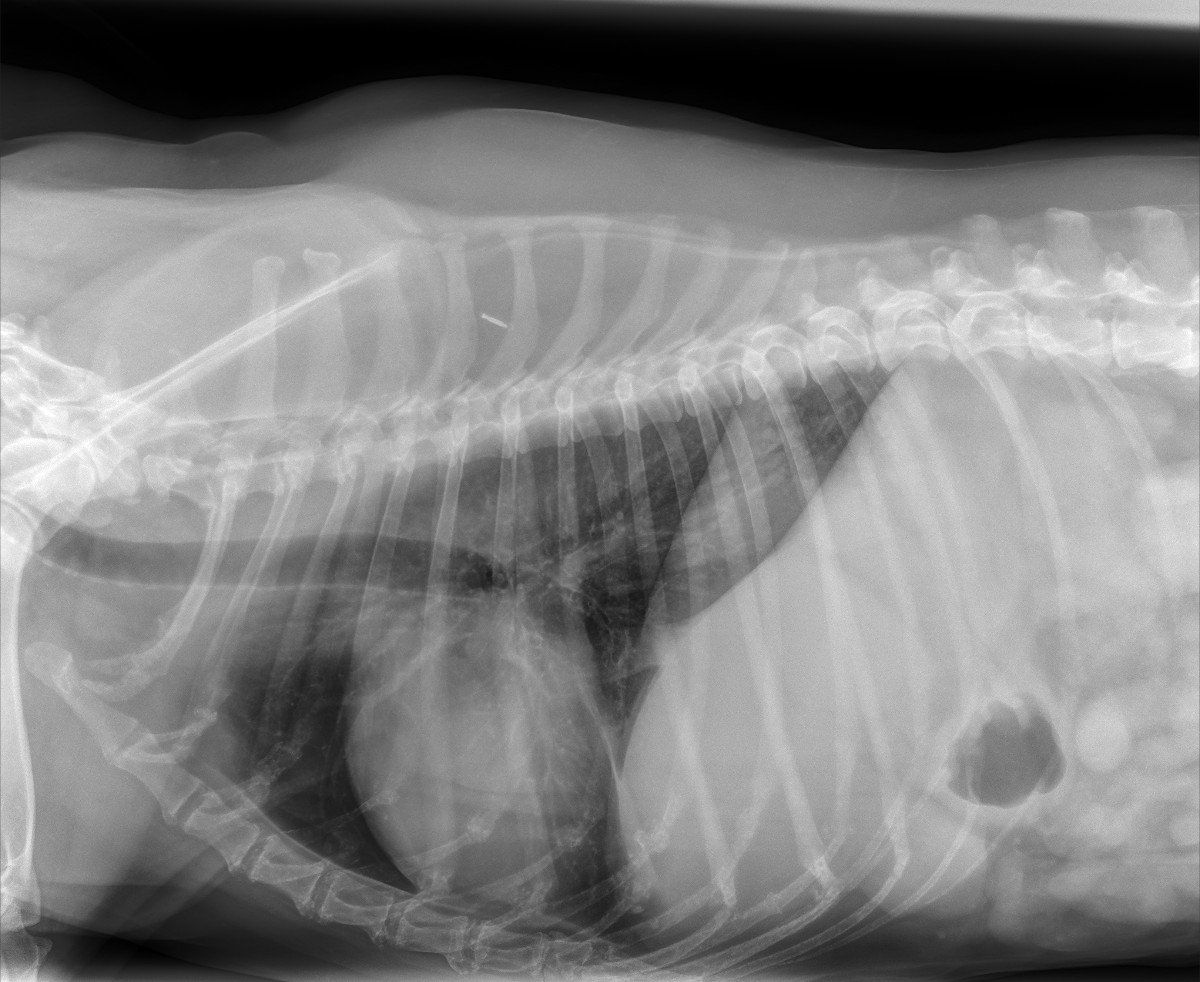

- Comprehensive Medical Care- Pet Dentistry- Advanced Pet Surgery

Medical Technologies